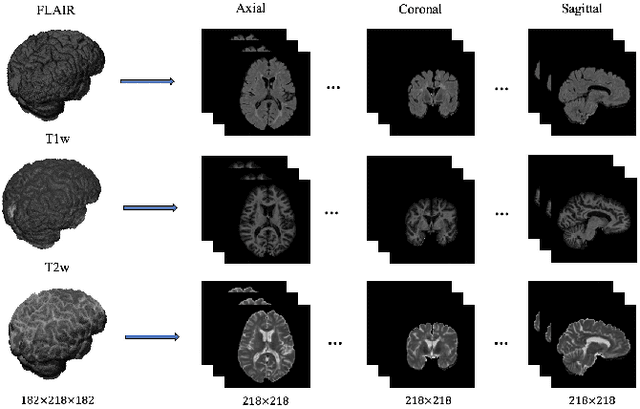

Abstract:In this paper, we present an automated approach for segmenting multiple sclerosis (MS) lesions from multi-modal brain magnetic resonance images. Our method is based on a deep end-to-end 2D convolutional neural network (CNN) for slice-based segmentation of 3D volumetric data. The proposed CNN includes a multi-branch downsampling path, which enables the network to encode slices from multiple modalities separately. Multi-scale feature fusion blocks are proposed to combine feature maps from different modalities at different stages of the network. Then, multi-scale feature upsampling blocks are introduced to upsize combined feature maps with different resolutions to leverage information from the lesion shape and location. We trained and tested our model using orthogonal plane orientations of each 3D modality to exploit the contextual information in all directions. The proposed pipeline is evaluated on two different datasets: a private dataset including 37 MS patients and a publicly available dataset known as the ISBI 2015 longitudinal MS lesion segmentation challenge dataset, consisting of 14 MS patients. Considering the ISBI challenge, at the time of submission, our method was amongst the top performing solutions. On the private dataset, using the same array of performance metrics as in the ISBI challenge, the proposed approach shows high improvements in MS lesion segmentation comparing with other publicly available tools.